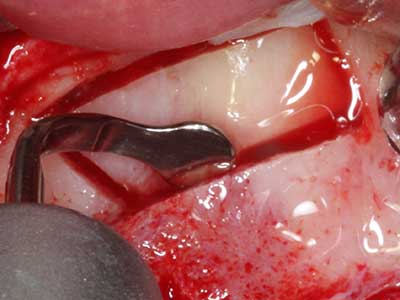

When surgical procedures are performed on bone in the immediate vicinity of sensitive structures such as blood vessels or nerves, rotary instruments pose a significant risk of iatrogenic injury. Piezoelectric devices can be helpful for preparation of bone covers and removal of hard tissue close to nerves, particularly for exposure of nerves after iatrogenic injury but also during nerve lateralization for resective and reconstructive procedures or implant placement (Fig. 17-20). Light contact between the piezotip and the nerve does not generally result in damage but proceeding incautiously with saw-like motions or attachments where a residual bone substrate remains may cause temporary or even permanent nerve damage. However, the risk of damage is considered to be substantially lower than when using saws or milling instruments (Pereira, Gealh et al. 2014).

Fig. 20: The removed bone cover is re-adapted and fixed with an osteosynthesis screw (KLS Martin, Tuttlingen).